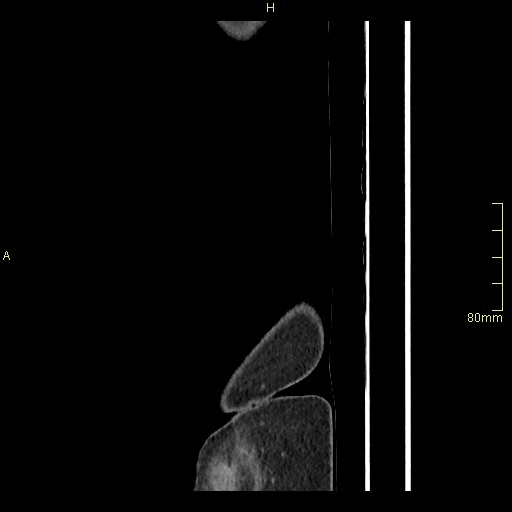

Abdomen Angiogram (Sagittal)